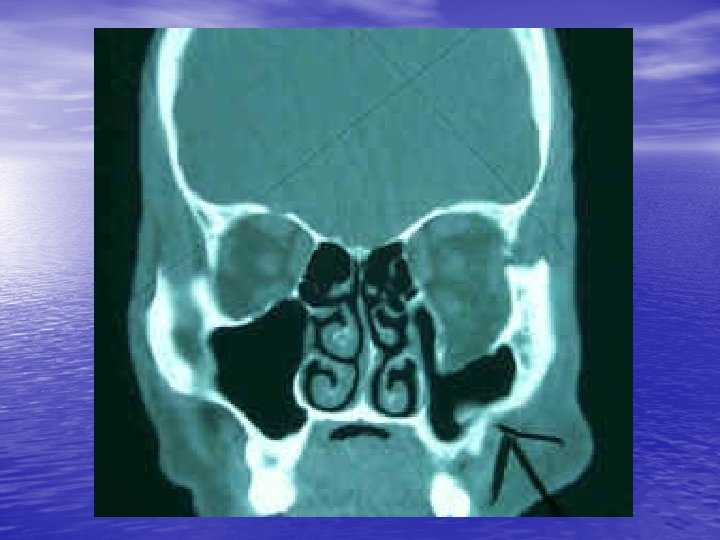

Retrobulbar Hemmorhage: • Hemmorhage in potential space surrounding • • globe may increase intraorbital pressure and cause CRAO. Symptoms=proptosis, visual loss, increased IOP Signs= CRAO Dx= above + orbital CT scan Tx=immediate optho consult, IV mannitol +/lateral canthotomy or anterior chamber paracentesis